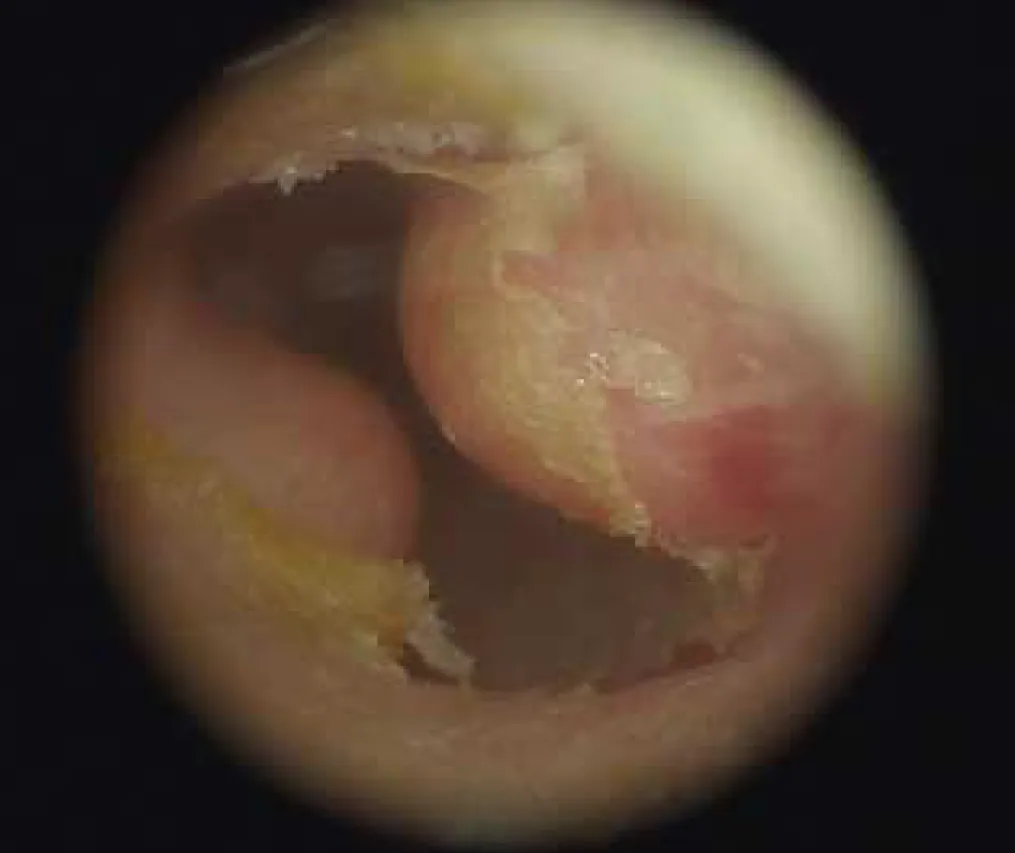

【113-1 醫學(六) 第20題】一中年男性長年四季晨泳,耳鏡檢查發現如圖,下列何者為最可能之診斷?

這題的解題核心在於將病患的「長期晨泳史」與耳鏡下看到的「外耳道骨性突起」連結起來。圖片中外耳道明顯可見多個表面光滑的骨性增生,這正是長期接觸冷水導致的典型表現。